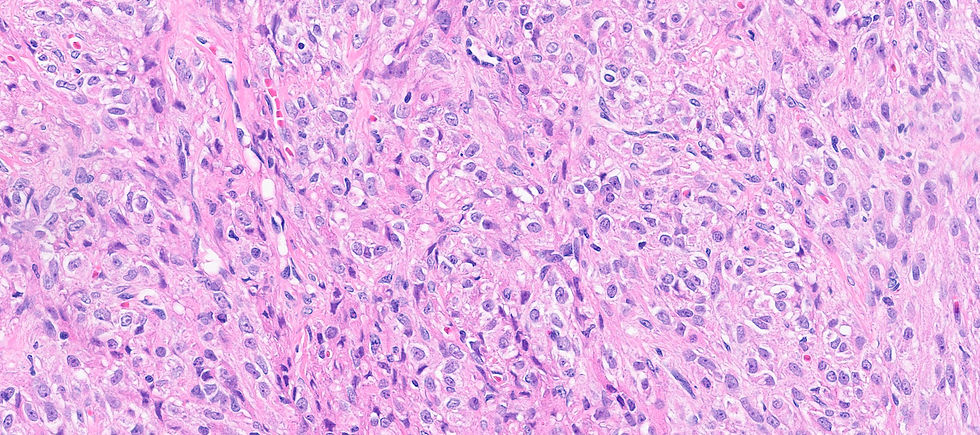

Before showing the IHC, putting the tumor into sex-cord stromal category is correct. However, the large solid nest architecture with irregular spindle to oval nuclei may clue you in a certain entity.

The final answer is F. Adult granulosa cell tumor (AGCT). AGCT can show various morphological patterns however, the most common pattern is diffuse, but cells may be arranged in cords or trabeculae; large solid nest, or forming microfollicular pattern with Call–Exner bodies. Nuclei groove is a reliable feature but it is not always seen. In this case of luteinized tumor show abundant eosinophilic cytoplasm and often lack nuclear grooves. The tumor cells are positive for FOXL2, calretinin, inhibin (although staining may vary in distribution and intensity), and SF1. Reticulin surrounds groups of cells rather than single cell in thecoma or fibroma.